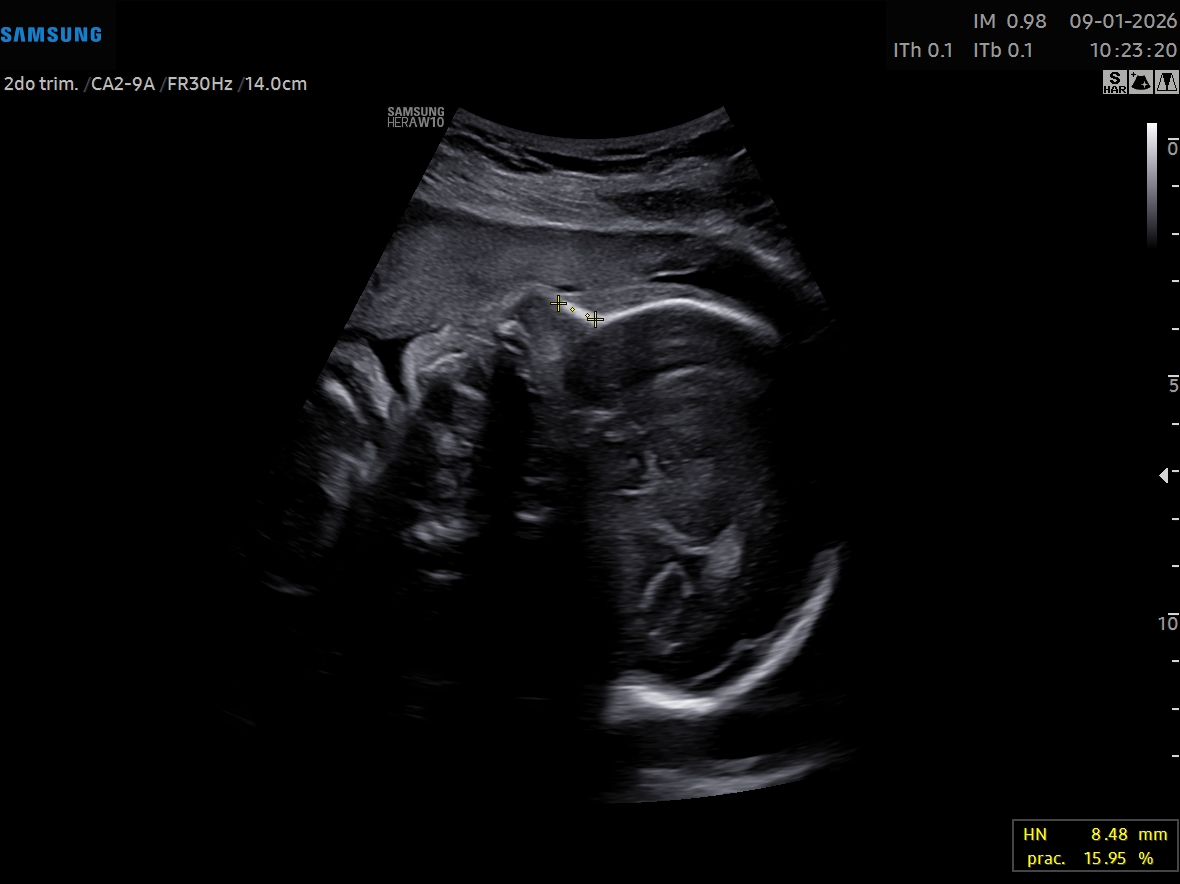

UN DULCE MILAGRO VIENE EN

CAMINO, ACOMPÁÑANOS A

CELEBRAR LA LLEGADA DE

NUESTRO PEQUEÑO TYLER dino gif